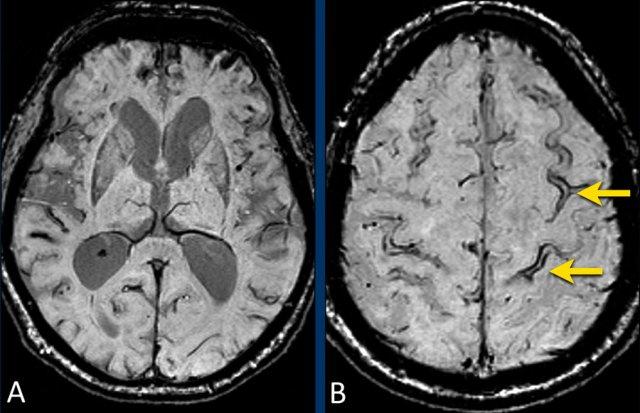

Nhiễm sắt bề mặt vỏ não trong CAA

Các ổ xuất huyết liên quan đến CAA bao gồm:

- Xuất huyết lớn (Macrobleeds) – xuất huyết thùy có triệu chứng lâm sàng

- Xuất huyết vi thể (Microbleeds) – nhỏ, thường không có triệu chứng, phân bố ở ngoại vi

- Nhiễm sắt bề mặt vỏ não (cSS) – xuất huyết dưới nhện vỏ não theo hình dạng cong của các hồi não xung quanh

Trong nhiễm sắt bề mặt, vị trí gần bề mặt vỏ não dường như là yếu tố khởi phát các triệu chứng thần kinh khu trú thoáng qua hay còn gọi là “cơn tinh bột” (amyloid spells).

Bệnh nhân CAA có nhiễm sắt bề mặt vỏ não lan rộng có nguy cơ xuất huyết tái phát cao hơn nhiều so với bệnh nhân không có cSS (tài liệu tham khảo).

Xuất huyết thùy trong bệnh lý mạch máu não dạng tinh bột (CAA)

Bệnh nhân CAA này nhập viện với hình ảnh khối máu tụ thùy lớn ở thùy thái dương phải.

Lưu ý hình ảnh nhiễm sắt bề mặt (mũi tên).